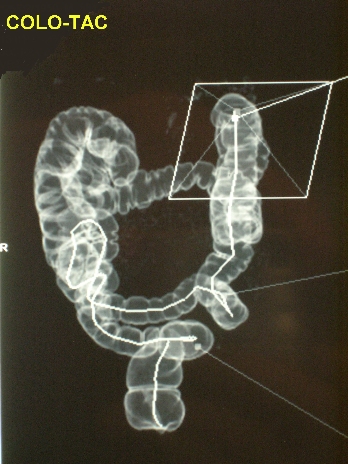

- COLO-TAC: Consiste en el estudio virtual del colon mediante imagen TAC. Está indicado fundamentalmente, al igual que el enema opaco, para estudiar el colon proximal en tumores de colon que no se han podido franquear con el colonoscopio y por lo tanto para descartar pólipos u otro tumor en el resto del colon no explorado. También tienen utilidad para localizar preoperatoriamente el tumor antes de la cirugía laparoscópica.